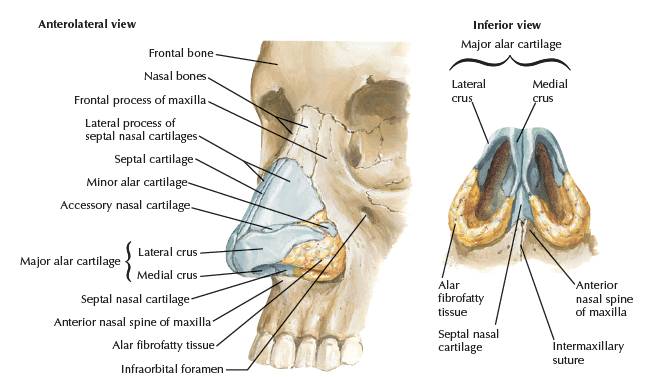

Bone

- Frontal (nasal process)

- Maxilla (frontal process)

- Nasal

Cartilage

- Septal

- Lateral nasal

- Alar

Artery

- Dorsal nasal a.

- External nasal a.

- Nasal br.

- Septal a.

- Alar a.

Nerve

- Ant. ethmoid n.

- Int./ Ext. nasal n.

- 鼻內/ 外感覺

- Int./ Ext. nasal n.

- Nasociliary br.

- Infraorbital n.

- Nasal br.